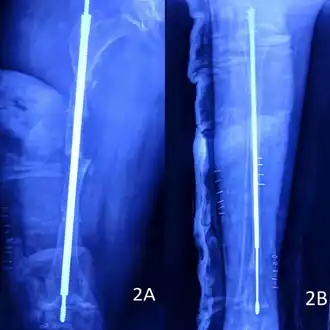

Metal rods can be surgically inserted in the long bones to improve strength, a procedure developed by Harold A. Sofield when he was Chief of Staff at Chicago's Shriners Hospitals for Children, a hospital that offers orthopedic care and surgery to children regardless of their family's ability to pay.[115] Large numbers of children with OI came to Shriners, and Sofield experimented with various methods to strengthen their bones.[116] In 1959, with Edward A. Millar [sic], Sofield wrote a seminal article describing a three-part surgery that seemed radical at the time: precisely breaking the bones ("fragmentation"), putting the resulting bone fragments in a straight line ("realignment"), then placing metal rods into the intramedullary canals of the long bones to stabilize and strengthen them ("rod fixation").[117] His treatment proved useful for increasing the mobility of people with OI, and it has been adopted throughout the world—it became standard surgical treatment for severe OI by 1979, in which year David Sillence found that ≈2⁄3 of the patients he surveyed with OI type III had undergone at least one rodding surgery.[42]: 108

Rodding surgery is often done with the hope that it will offer a path to ambulation, walking, to patients with moderate or severe OI. A 2020 review in The Journal of Bone and Joint Surgery (JB&JS) found it remains broadly popular: ≈2⁄3 of people with OI types III and IV (severe OI) have undergone some form of rodding surgery in their lives, at a mean age of 4+1⁄10 and 7+1⁄2 years respectively;[25]: Table I one possible explanation for a tendency towards earlier intervention in type III is that one half of affected children could not walk at all without the surgery, as their limbs were more bowed, so surgery was sought sooner.[25]

In those with type III OI who had undergone rodding surgery, 79.5% had the femurs and tibias of both legs rodded.[25]: Table I The most common form of rods used are intramedullary (IM) rods, some of which, such as the Fassier–Duval IM rod, are telescoping, meaning that they are designed to grow as the child grows, in an attempt to avoid the necessity of revision surgeries.[118] Telescoping IM rods are widely used,[119] and the common Fassier–Duval IM rod is designed to be used to rod the femur, tibia, and humerus.[120]: 1 The surgery involves breaking the long bones in between one and three (or more)[119]: Figure 4 places, then fixing the rod alongside the bone to keep it straight.[120]: 11

While telescoping IM rods are intended to grow along with both the femur and tibia in developing children; surgeons have a preference to use non-telescoping IM rods, such as Rush rods, in the tibia, which grows less comparatively—the JB&JS review found that while 69.7% of femurs were treated with telescoping IM rods, only 36.9% of tibiae were.[25]: Table IV